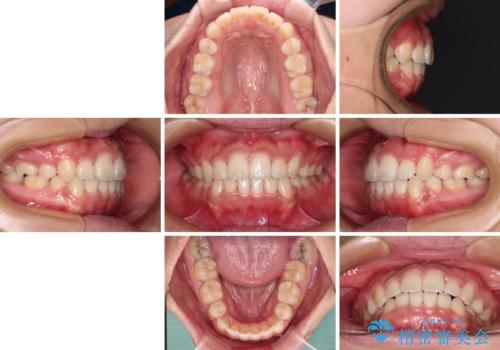

気になる八重歯を治したい 目立たないワイヤーでの抜歯矯正

非常にスムーズに歯列移動が行われ、当初は2-2.5年を予想していましたが、僅か1年4ヶ月で治療を終えることができました。